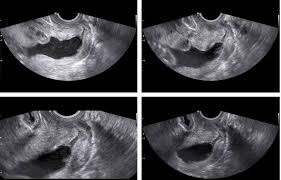

1- سونوگرافی ترانس واژینال: جهت تولید تصاویر سونوگرافی در داخل واژن مورد استفاده قرار می گیرند که ترانس واژینال اغلب در دوران اولیه بارداری استفاده می شود.

در سونوگرافی واژینال، برای گرفتن تصاویر بهتر از رحم و تخمدان های فرد، یک مبدل استوانه ای در واژن خانم قرار می گیرد.